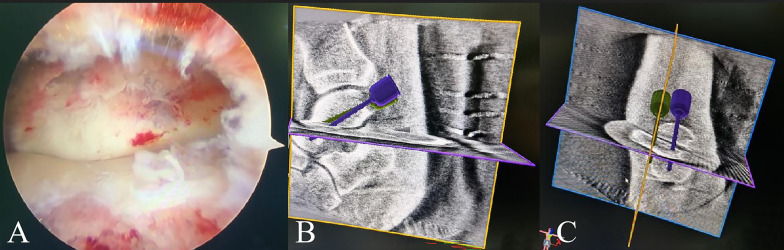

Purpose: To investigate the effect of arthroscopic reduction combined with robot-guided screw placement on Hawkins type II fractures of the talus neck.

Methods: Clinical data from 42 patients with talus neck Hawkins type II fracture treated in the institution from November 2019 to January 2021 were selected. According to the blind envelope method, 21 patients were enrolled in the study group, and 21 patients were enrolled in the control group. The patients in the study group underwent arthroscopy-assisted reduction combined with orthopedic robot navigation screw placement surgery, while those in the control group underwent open reduction surgery.

Conclusions: The management of Hawkins type II fracture of the talus neck using arthroscopy-assisted reduction combined with robot navigation screw placement yields satisfactory results and represents a viable treatment alternative that warrants consideration.